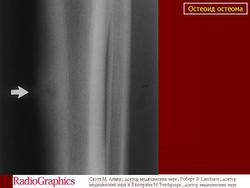

На иллюстрации показана доброкачественная периостальная реакция при остеоид остеоме.

Доброкачественная периостальная реакция

Определение доброкачественности периостальной реакции очень важно, так как злокачественные опухоли никогда не вызывают доброкачественной периостальной реакции.

Доброкачественная периостальная реакция представляет собой довольно плотное и равномерное (по структуре) образование «каллуса» (новой костной ткани) и в результате хронического раздражения, надкостница успевает «сложить» новую костную ткань кортикального слоя (параллельно оси кости), придавая ей более, или менее «нормальный вид».

Поднадкостничная остеоид остеома большеберцовой кости, в области диафиза у 18-летнего мужчины.

Рентгенограмма фиксирует рентгенопрозрачные очаг (стрелка) на фоне веретеновидного коркового утолщения.